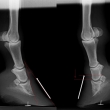

Těžká artróza ve spěnkovém kloubu

Chronicky schvácené kopyto